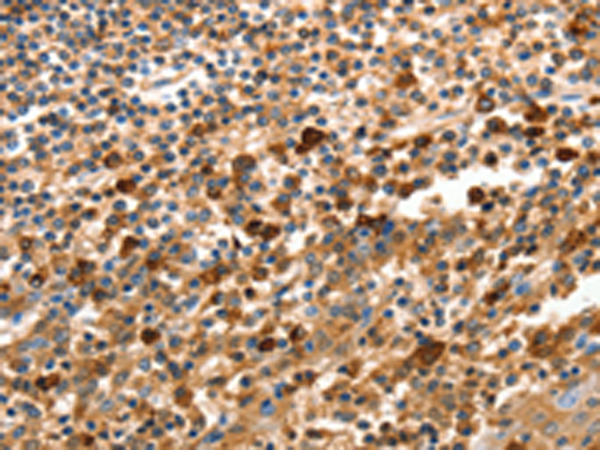

分类: 科研抗体货号: P11242别名: ARB1; ARR1应用: WB,IHC反应种属: Human, Mouse, Rat